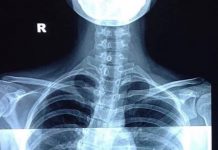

Đột quỵ xảy ra khi nguồn cung cấp máu cho một phần não của chúng ta bị giảm hoặc mất hoàn toàn do mạch máu não bị tắc hoặc bị vỡ, dẫn đến các mô não không nhận được oxy và chất dinh dưỡng, tế bào não bắt đầu chết dần trong vài phút.

Có hai loại đột quỵ chính theo thương tổn đó là: Thể mạch máu não bị tắc nghẽn (Nhồi máu não) và thể mạch máu não bị vỡ (Xuất huyết não). Một số người có thể chỉ bị gián đoạn tạm thời lưu lượng máu đến não, gọi là cơn thiếu máu cục bộ thoáng qua (Transients Ischemic Attack-TIA), chúng thường không gây ra các triệu chứng lâu dài tuy nhiên đây cũng là “điềm báo” về nguy cơ chúng ta bị đột quỵ về sau nếu không được dự phòng sớm. Nhồi máu cơ tim (Heart Attack hay Myocardial Infarction) về cơ chế giống như thể nhồi máu não, tức là các tế bào cơ tim bị thiếu máu cấp tính do mạch nuôi tim (Mạch vành) bị tắc nghẽn dẫn đến tim bị “chết” một phần hoặc toàn bộ và tử vong rất nhanh.